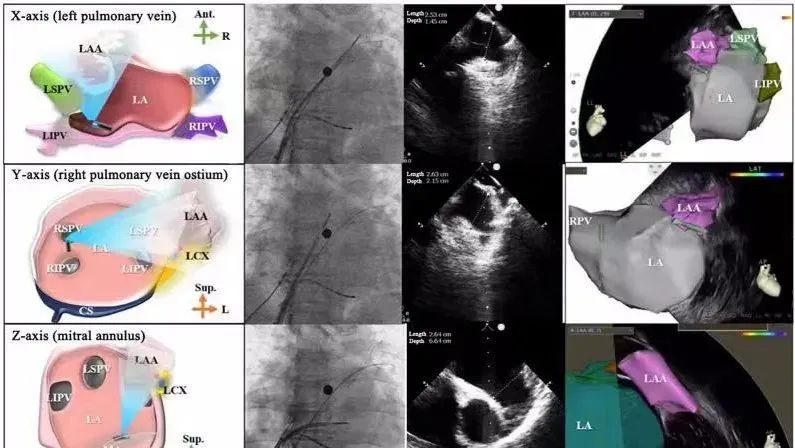

一種與心導(dǎo)管檢查相結(jié)合的超聲心動(dòng)圖診斷新興技術(shù),通過將超聲探頭置于心腔內(nèi)部,發(fā)射并接收超聲信號(hào),來精確獲取心臟解剖結(jié)構(gòu)、心臟血流動(dòng)力學(xué)等信息的實(shí)時(shí)成像。與其他影像技術(shù)相比,ICE技術(shù)具有操作簡單、無輻射、安全性高、手術(shù)效率高、實(shí)用等優(yōu)勢(shì),ICE在很大程度上有望取代經(jīng)食道超聲心動(dòng)圖(TEE),成為電生理和結(jié)構(gòu)性心臟病領(lǐng)域的理想成像方式。

目前ICE技術(shù)已被應(yīng)用于左心耳封堵、房顫射頻消融、二尖瓣成形、房間隔缺損封堵等多種心臟介入手術(shù),應(yīng)用場景主要圍繞臟電生理、結(jié)構(gòu)性心臟病等領(lǐng)域,目前以電生理應(yīng)用為主。數(shù)據(jù)顯示,我國結(jié)構(gòu)性心臟病介入器械市場規(guī)模已從2017年的4億元增長至2021年的20億元,年復(fù)合增長率達(dá)48.3%;預(yù)計(jì)到2025年,該市場規(guī)模將達(dá)到104億元,可以預(yù)見ICE市場規(guī)模也將同步高速增長,未來市場發(fā)展空間廣闊。

心腔內(nèi)超聲(ICE)技術(shù)壁壘極高,國內(nèi)主要廠商核心部件仍舊為進(jìn)口,集成了超聲和圖像處理最前端技術(shù),包括超聲探頭、線纜、軟件成像算法等,是當(dāng)前內(nèi)窺超聲方向最具挑戰(zhàn)的領(lǐng)域。ICE的應(yīng)用經(jīng)歷了2D平面成像、3D三維立體成像、以及4D的實(shí)時(shí)三維立體成像階段。